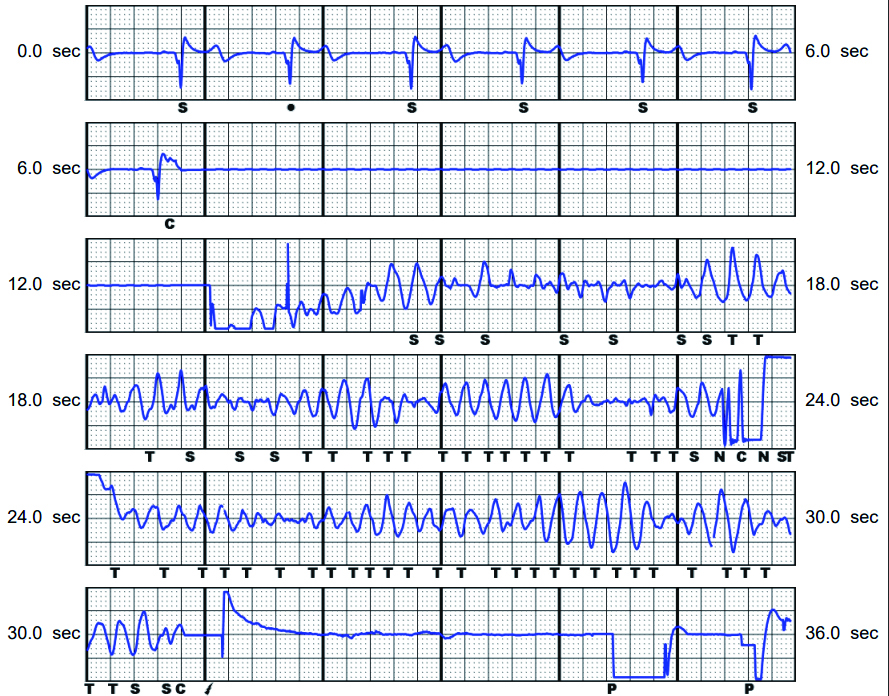

术前DSA透视体表定位(图 2),行腋中线第4~6肋间纵切口及剑突上3 cm横切口,以隧道针将除颤导线感知环头端送至胸骨柄,除颤器(波科S-ICD A209)与导线相连后置于囊袋固定。程控显示导线感知、高压阻抗正常。选择Secondary为感知向量,DFT测试:以50 Hz直流电诱发室颤,S-ICD以65 J一次转复,时长共14 s(图 3),高压阻抗37 Ω。无血管活性药物应用下暂停ECMO,心超评估EF 64%,心率100次/min,血压92/43 mmHg,SpO2 99%,撤离ECMO。术后1 d撤离呼吸机,患儿神志清,反应可,对答切题,四肢活动良好,术后6 d转入心衰病房,2024-01-23出院,住院共32 d。本文报道已取得患者监护人知情同意,伦理审批号为2020-IRB-006。

| 图 3 S-ICD植入后程控诱颤及除颤过程 |